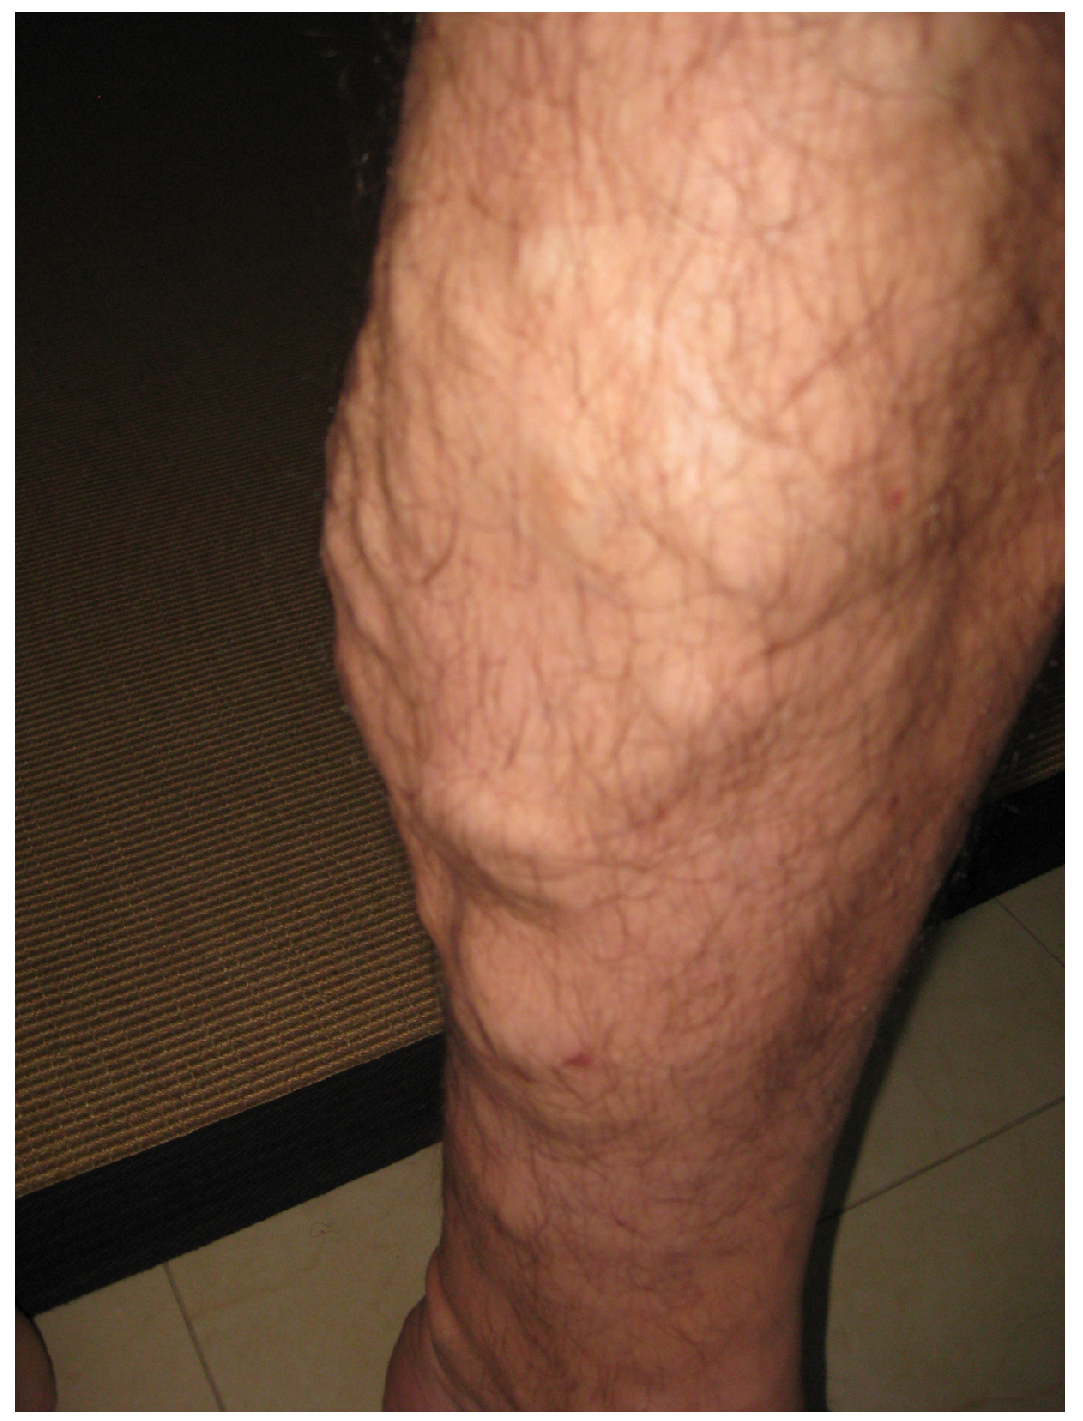

Varicose veins are commonly found in the lower limbs. (credit: Thomas Kriese) - (6) Capillary Bed

- Venous disorders – Varicose Veins

- Irregular, dilated, & tortuous areas of superficial veins in legs

The illustration shows how a varicose vein forms in a leg. Figure A shows a normal vein with a working valve and normal blood flow. Figure B shows a varicose vein with a deformed valve, abnormal blood flow, and thin, stretched walls. The middle image shows where varicose veins might appear in a leg. -

- Appear as irregular, purplish, bulging structures

- Edema in feet